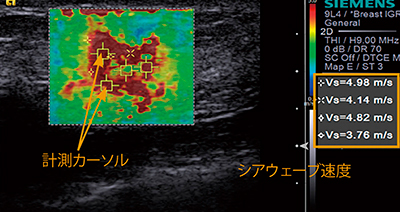

●シアウェーブエラストグラフィ

用手的な加振が不要であるため,操作者の手技に依存するところが少ないエラストグラフィです。視覚的な組織弾性イメージングに加えて,シアウェーブ伝搬速度によって局所の組織硬度を定量的に評価することが可能です(図3)。

図3 シアウェーブエラストグラフィ